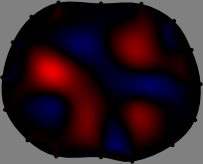

Figs. 3 and 4 compare the performance of the proposed FER method in (20) with the standard regularized least-squares method ((19) when \mathcal{R} is the identity matrix). The regularization parameter of the standard method was heuristically chosen for its best performance, and the parameter of the FER method was set to be one of three different values λ=0.05,0.2,𝜆0.050.2\lambda=0.05,0.2,\infty. The injection current was 1 mARMSRMS{}_{\tiny{\mbox{RMS}}} at 100 kHz, and the frame rate was 9 frames per second. The reference frame at t0subscript𝑡0t_{0} was obtained from the maximum expiration state. The measured data, 𝐕˙(tm)˙𝐕subscript𝑡𝑚\dot{\mathbf{V}}(t_{m}), represent the voltage differences between each time tmsubscript𝑡𝑚t_{m} and t0subscript𝑡0t_{0}. The blue regions, which denote where conductivity decreased by inhaled air, increased during inspiration and decreased during expiration. The FER method with λ=𝜆\lambda=\infty was clearly more robust than the standard method that produced more artifacts originated from the inversion process.

Figure 4: The reconstructed images of the conductivity change of the subject B by the standard regularized least square method and the proposed fidelity-embedded regularization (FER) method for three difference values λ=0.05,0.2,𝜆0.050.2\lambda=0.05,0.2,\infty. Here, the time step is 0.55 seconds (tm+5tm0.55subscript𝑡𝑚5subscript𝑡𝑚0.55t_{m+5}-t_{m}\approx 0.55).